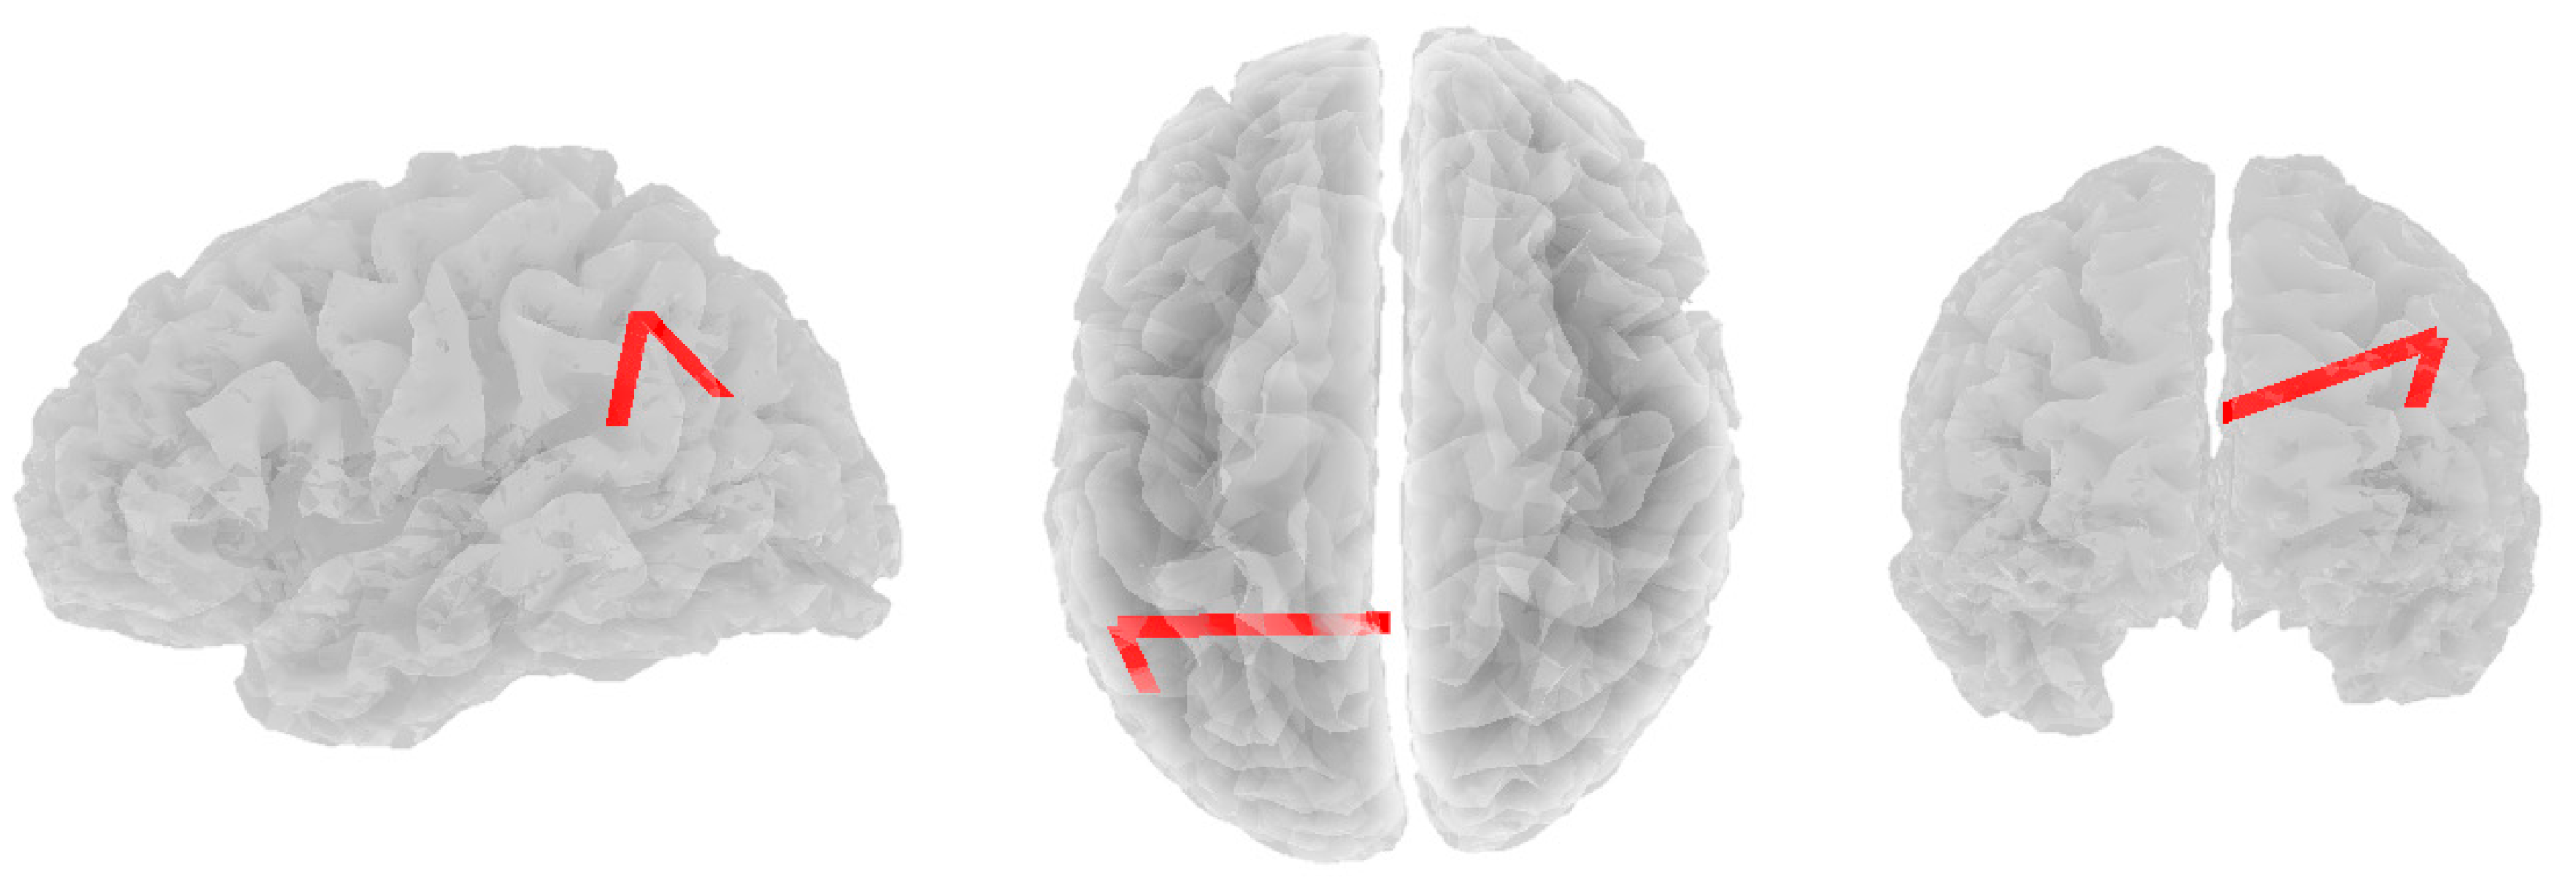

3.2. Alpha Band

3.3. Beta Band

3.4. Theta Band